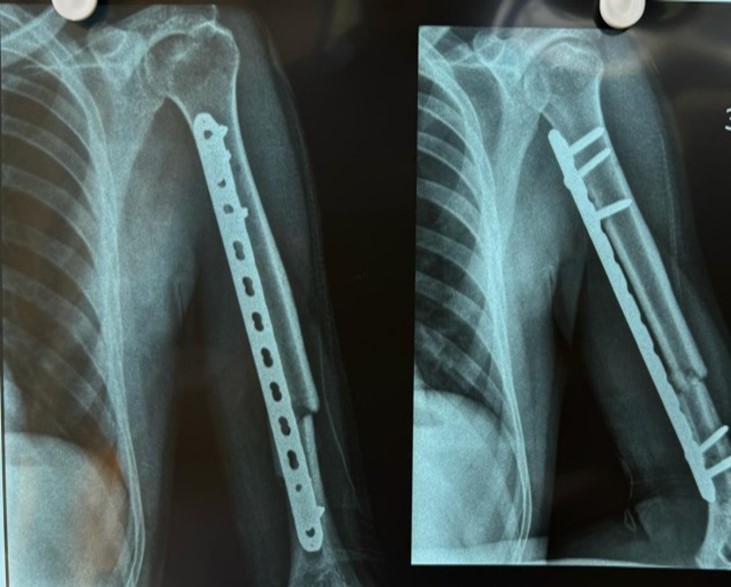

35 year old male patient suffering from closed displaced diaphyseal humerus fracture without distal neurovascular deficit. Follow up was taken at 3months post operatively and 12 months post operatively

3 months follow up